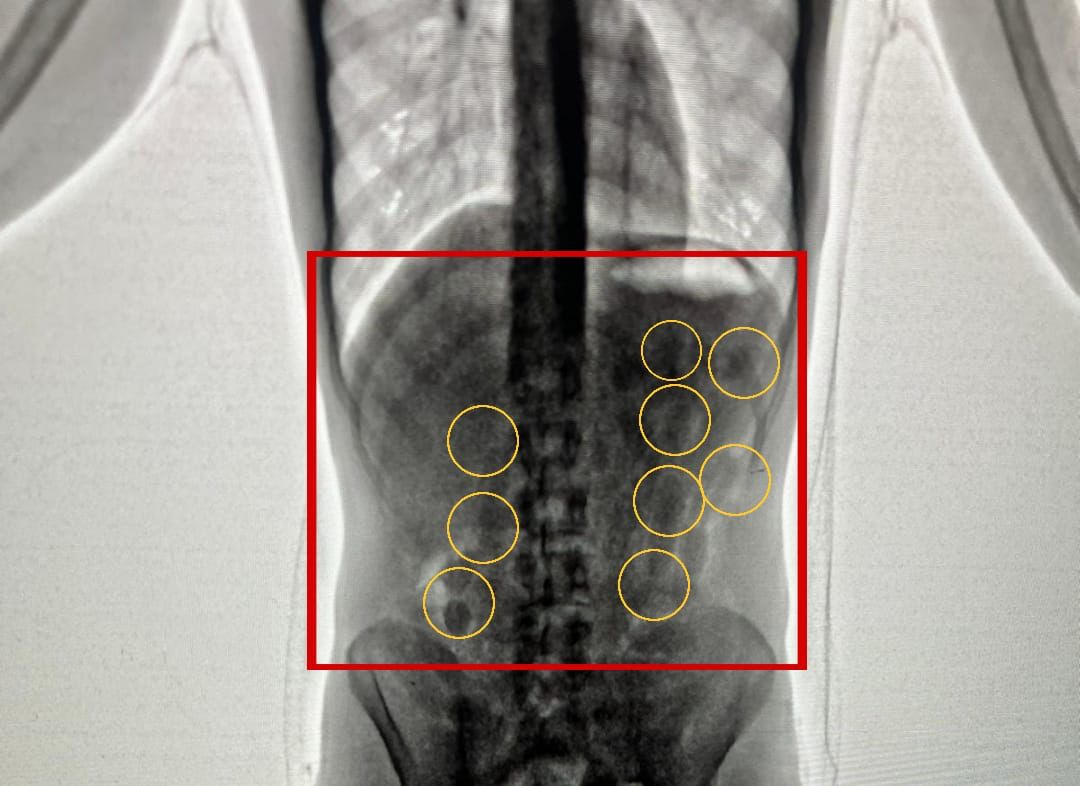

وبعد تفتيشهما والكشف عليهما بواسطة الاجهزة اللازمة اكتُشف وجود كميات من المواد المخدرة داخل أحشائهما ، وجرى إخراج هذه المواد بالطرق الطبية، وقُدرت ب 2 كغم من مادة الكوكايين المخدرة .